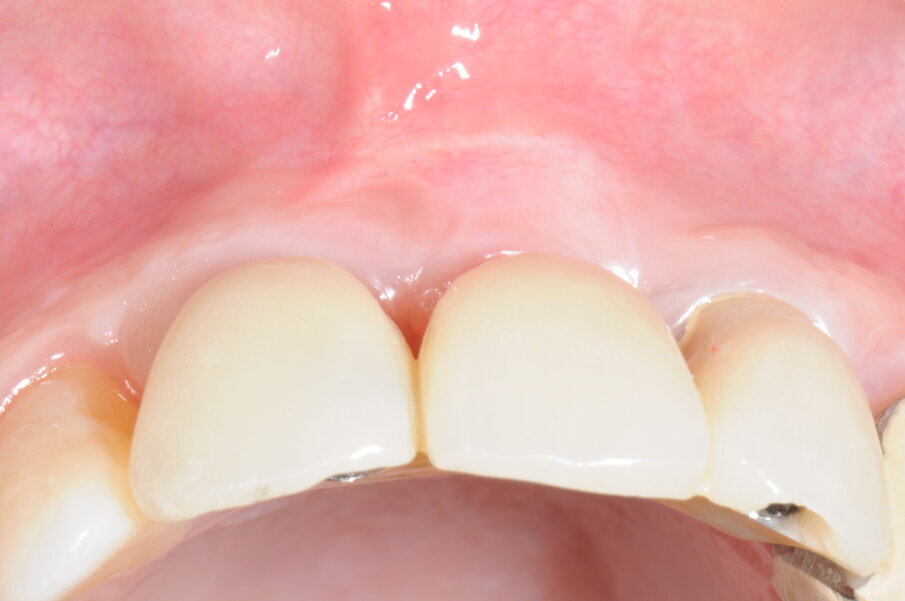

Trenta giorni dopo è stata rilevata l’impronta di precisione per la realizzazione di un provvisorio rinforzato in metallo che garantisse il ripristino della funzione masticatoria, estetica e fonetica (Figg. 20-25b).

Figg. 24a, 24b - Protesi provvisoria in visione occlusale e frontale.